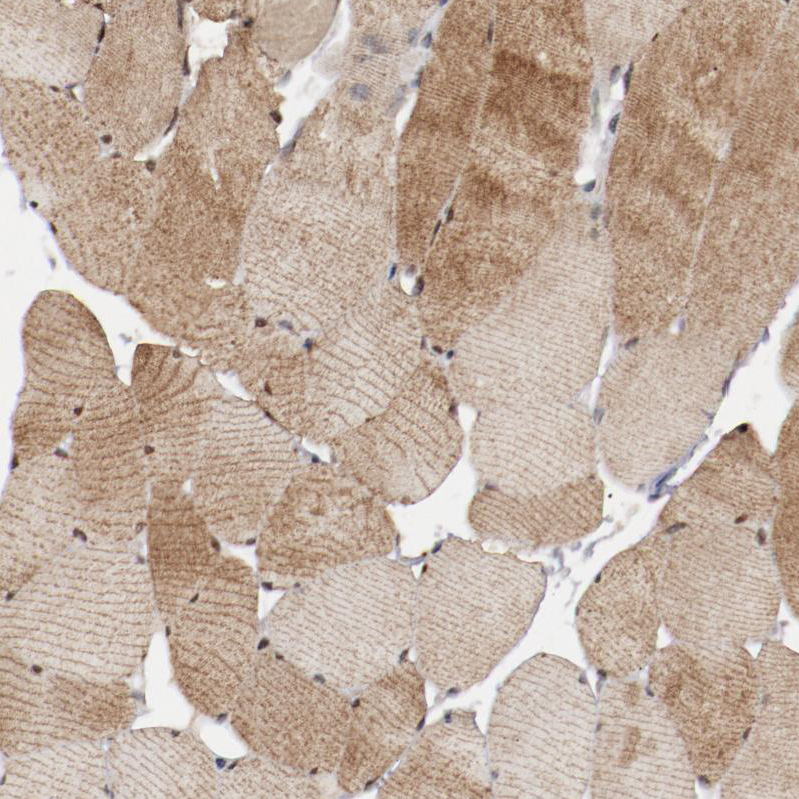

Immunohistochemistry analysis in human heart muscle and prostate tissues using HPA001765 antibody. Corresponding MYOM2 RNA-seq data are presented for the same tissues.